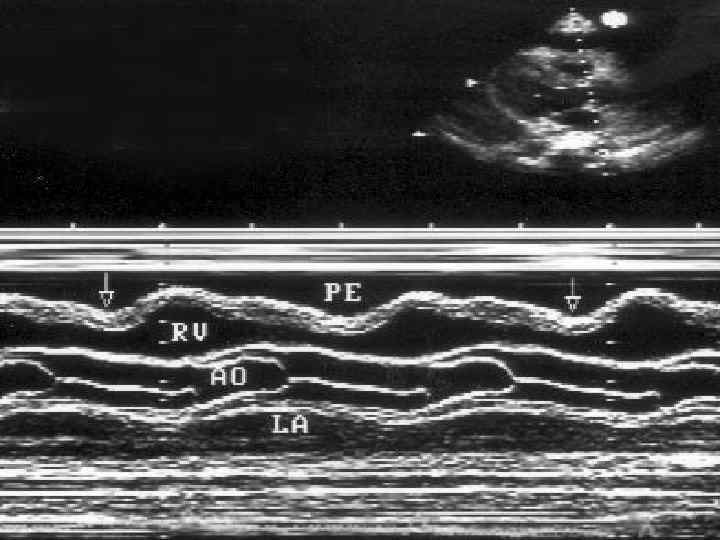

ЭХОКС при сухом перикардите • Утолщение листков перикарда с последующим появлением расслоения листков

ЭХОКГ • Увеличение количества жидкости в перикарде • Расслоение листков перикарда от 3 мм до 2 -3 см • Яркое свечение листков перикарда • Утолщение листков перикарда • Появление диастолической дисфункции миокарда • Втяжение стенки правого желудочка при тампонаде сердца

ЭХОКС • Выпот в полости перикарда может располагаться циркулярно вокруг сердца или инкапсулированно перед отдельными полостями сердца. • При отсутствии спаек и свободном движении жидкости в полости перикарда сепарация листков максимальна позади левого желудочка и у верхушки сердца, постепенно уменьшается и исчезает на уровне основания сердца. • При выпоте отмечается повышенная экскурсия задней стенки ЛЖ, а у части больных гиперкинезия передней стенки правого желудочка и межжелудочковой перегородки.

• Основное диагностическое значение имеет диастолическое расхождение листков перикарда, которое может быть выявлено при количестве выпота, превышающем 15– 35 мл. Градации выраженности выпота: • 1) малый (расхождение листков перикарда <10 мм); • 2) умеренный (≥ 10 мм кзади); • 3) большой (≥ 20 мм); • 4) очень большой (≥ 20 мм плюс симптомы сдавления сердца) - тампонада

ЭХОКС Полуколичественная оценка объема перикардиального выпота: • циркулярное эхонегативное пространство (сумма величин сепарации листков перикарда по передней и по задней поверхности сердца в конце диастолы) - • менее 5 мм — незначительное количество жидкости (менее 50 мл); • 5– 10 мм — небольшое количество (50– 100 мл); • 10– 20 мм — умеренное количество (100– 300 мл); • более 20 мм — значительное количество (более 300 мл).

ЭХОКС • При наличии небольшого выпота в перикарде обнаруживается относительно свободное от эхо-сигнала пространство между задней частью перикарда и задней частью эпикарда левого желудочка. • При большем объеме выпота это пространство располагается между передней частью перикарда правого желудочка и париетальной частью перикарда непосредственно под передней грудной стенкой.